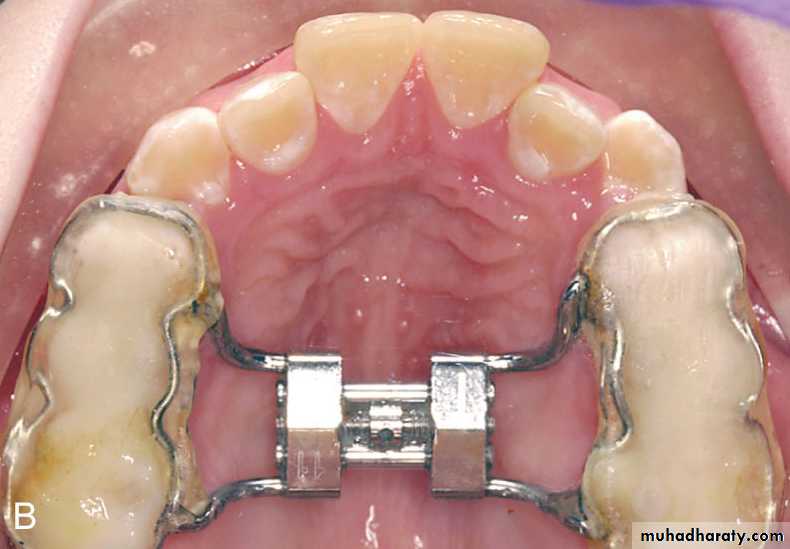

In this age sutural expansion require placing a relatively heavy force across the suture.This is achieved using fixed expander with rigid jackscrew. The appliance should include as many teeth as possible in anchorage unit.

It is activated to produce slow expansion since its more physiologic and effective in these young patients

In this age slow and rapid expansion can be used. However, as the patient matures heavy forces and more rapid activation is required to open the suture.• Bonded or banded expander. (can produce both rapid and slow expansion)